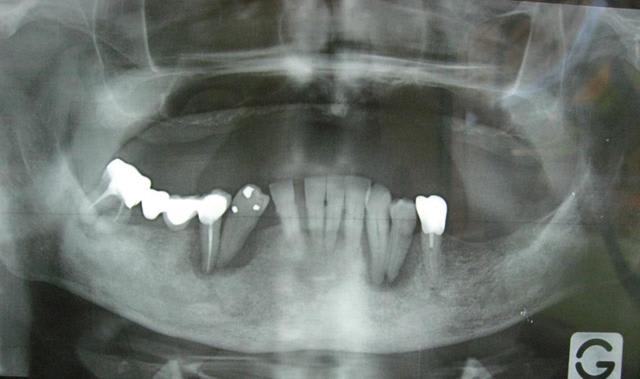

Patient vu en début d'année, parodontite en phase terminale, "monsieur je pense qu'il faudrait vous enlever quelques dents" (voir pano). Lui pas trop pressé apparemment.

Il revient me voir ce mois-ci pour faire sa prothèse. Je lui dit qu'il faut extraire ses dents d'abord.

Il me répond : "ah ben non, elles sont déjà tombées, mais je les garde en bouche ... en attendant!"

Et donc à chaque étape, empreinte, RIM, essayage, je demandais à monsieur d'enlever ses dents, qu'il remettait en place à la fin de la séance.

Du jamais vu pour moi, même si je suis encore jeune dans le métier!!

Fallait que je fasse partager!